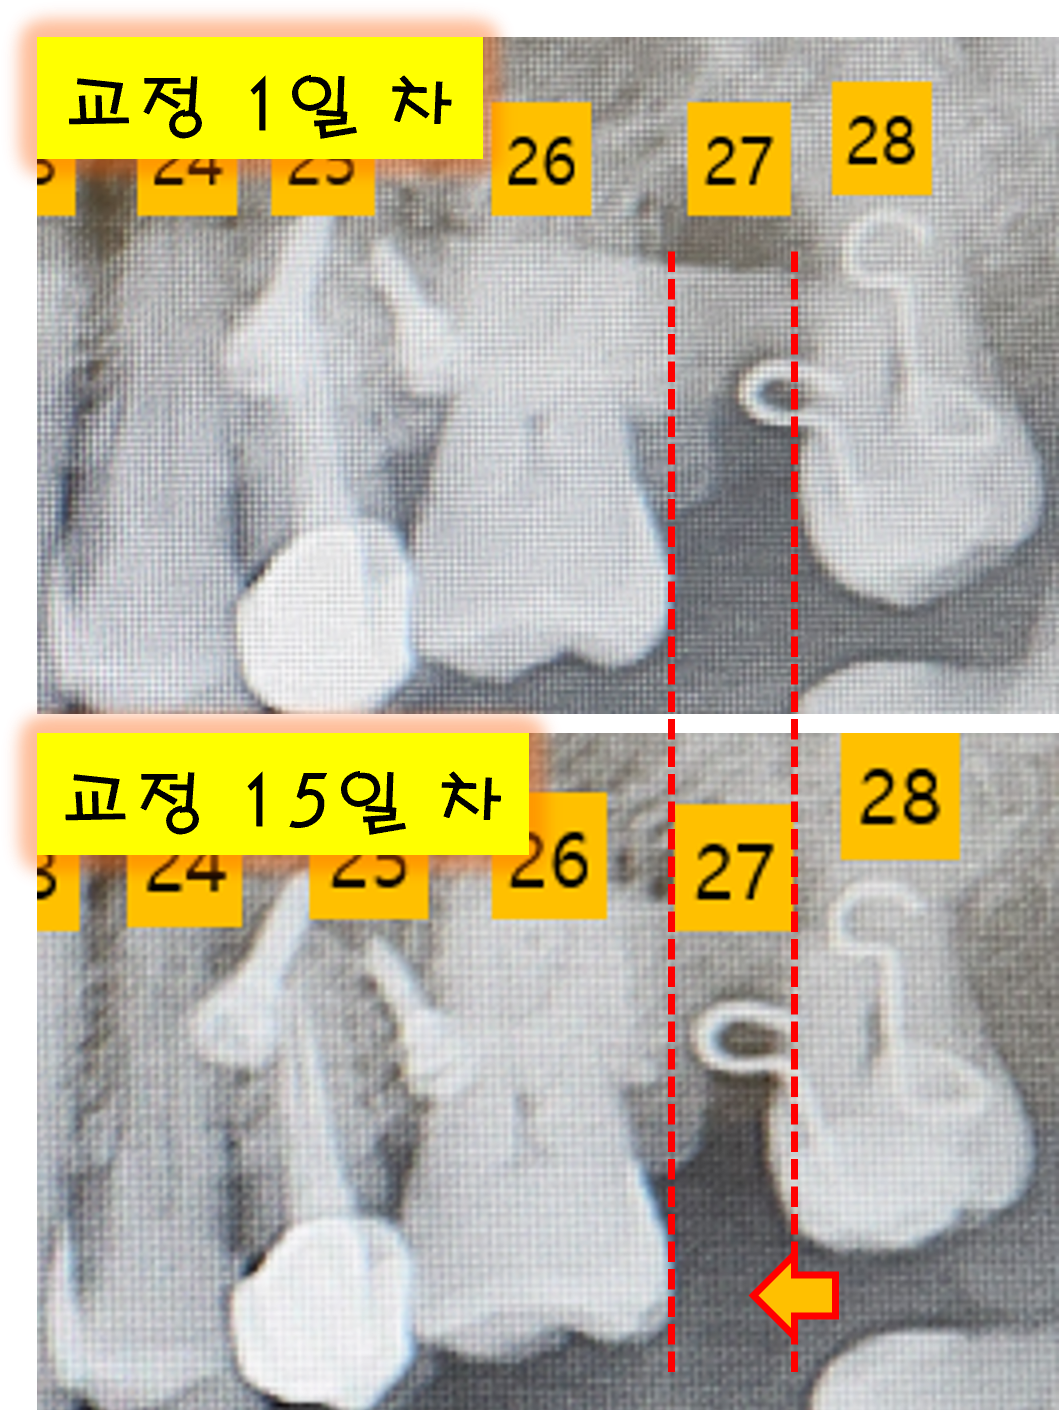

교정 상태 확인

잠시 마취가 되는 동안, 교정 상태를 확인 한다고 합니다.

이 병원이 좋은 점은 치과 치료와 교정 치료를 동시에 받을 수 있어서입니다. 교정 부분에 대해 깨끗하게 스케일링을 진행한 후 상태를 확인하였습니다. 아주 미세하지만 28번 치아가 빈 공간인 27번 쪽으로 이동이 되어 있네요. 생각보다 빠르게 빈 공간이 메꾸어지고 있는 것을 보니 기분이 그나마 좋습니다.

교정 15일차 변화.png [교정 시작과 15일 차를 비교한 파노라마 사진]